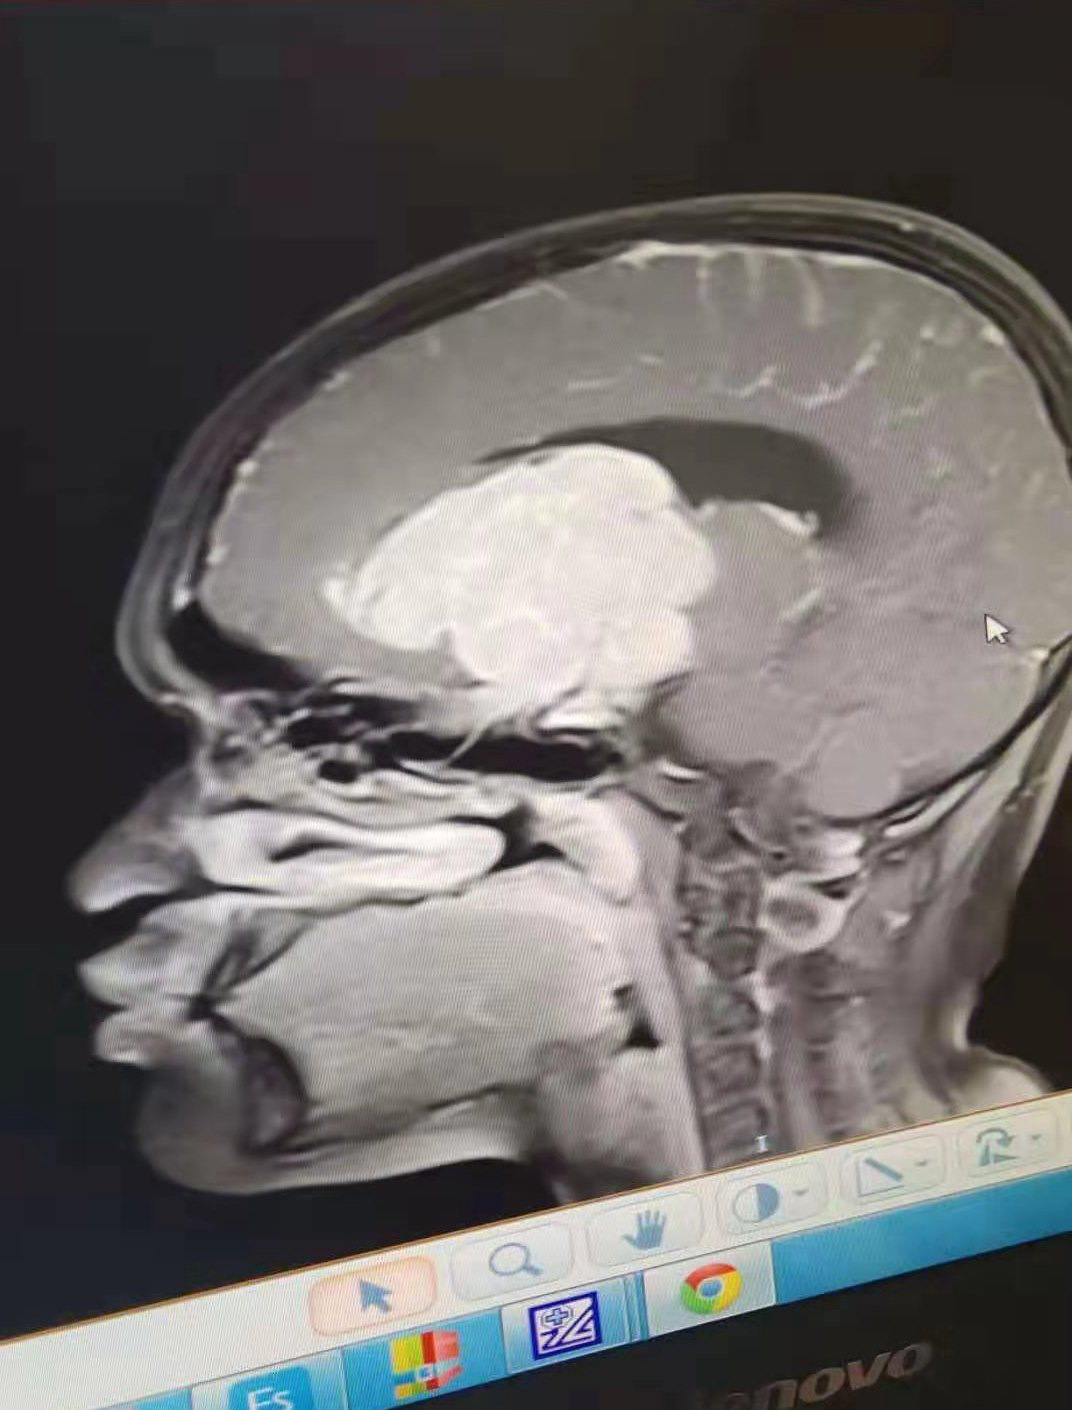

记者1224日从清镇获悉,“水医堂”将救助16垂脑垂体生殖细胞瘤和脑积水的贵州松桃县苗族姑娘吴柔。

2015年,贵州松桃县乌罗镇前进村的苗族残疾姑娘吴柔,不幸患上脑垂体生殖细胞瘤和脑积水。20191215日,因病导致视力残疾的吴柔住进铜仁市人民医院,医院下达了病危急(重)通知书后,父亲吴承勇和家人四处奔波寻找救助。经贵州吴文化研究会吴学强会长推荐,“水医堂”愿意接收并救助16脑垂体生殖细胞瘤和脑积水姑娘吴柔。

生殖细胞瘤由原始的生殖细胞衍生而来,好发于松果体区,其次为鞍上池。肿瘤多发生于男性青少年,位于鞍上生殖细胞瘤则以女性多见。生殖细胞瘤对放射线非常敏感。该瘤通常无包膜、无钙化、出血、坏死或囊性变,属低度恶性肿瘤,多呈浸润性生长,常有不同程度和形式的转移,易向蛛网膜下腔及脑室系统种植、播散。生殖细胞瘤可早期压迫或梗阻导水管的上端开口,引起梗阻性脑积水,当肿瘤进一步增大时,压迫第叁脑室后部或导水管上端,使梗阻性脑积水更为突出,因此,几乎所有的病人都有颅内压增高的症状及体征。主要表现为头痛、恶心呕吐、复视、视盘水肿,小儿可有头围扩大等。后期可继发视神经萎缩及展神经麻痹等。最常见的定位症状有Parinaud 综合征,这是Parinaud 1883 年首先指出松果体区肿瘤可出现上视不能、瞳孔光反应和调节反应障碍等。其中部分病人同时合并下视不能,瞳孔光反应迟钝或丧夫、调节反应减弱及阿罗瞳孔是生殖细胞瘤的重要体征。约半数以上的病人可出现小脑症状,表现为持物不稳、走路摇晃、眼球震颤等,少数侵犯基底节时可出现偏瘫等。肿瘤压迫下丘脑及内侧膝状体可出现双侧耳鸣及听力下降。